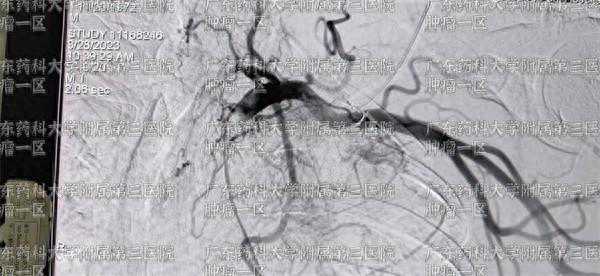

而中晚期的肺癌患者,微创手术中,动脉灌注栓塞治疗,氩氦刀冷冻消融治疗、微波消融治疗更为常见。对中晚期的肺癌患者,广东药科大学广州复星禅诚医院肿瘤一区医生通常会在会诊后,结合患者的病情,选择其中一个或几个微创技术相结合,并适当加入免疫、靶向、中医、富血小板抗肿瘤治疗等整体质量,组合为综合治疗方案进行。

彭齐荣教授表示,中晚期肺癌患者的治疗通常采用多种治疗方式进行综合治疗,结合患者具体病情以及病理类型,综合考虑肿瘤的分期、患者的身体状态等制定综合治疗方案。